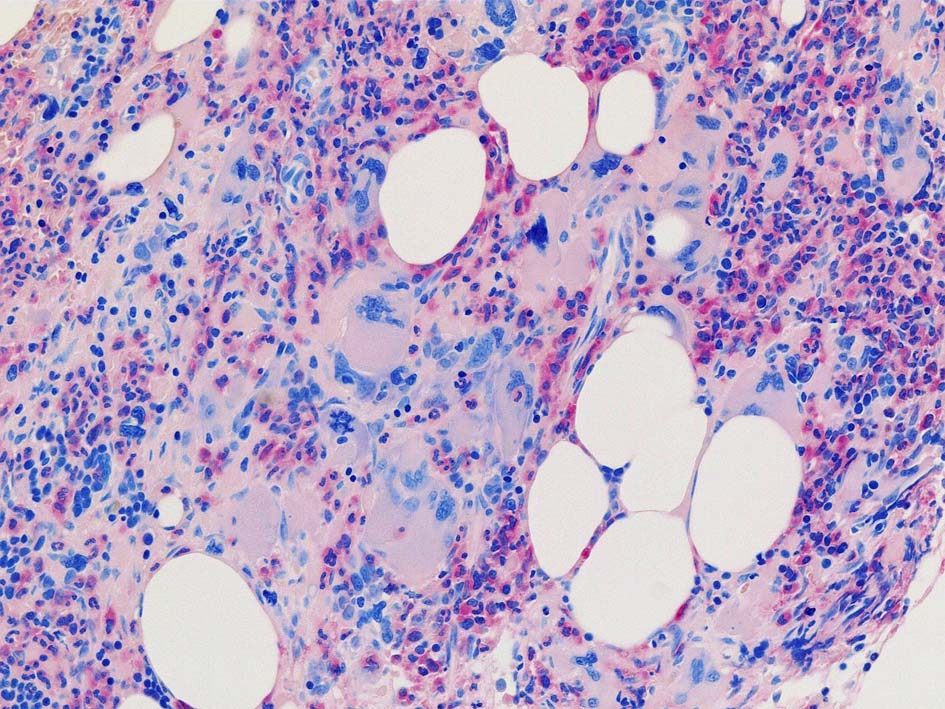

Case01; Meylofibrosis, overt fibrosis

77year-old female. 40歳時polycythemia veraと診断されていた.

[注] この症例は詳細は不明であるが, 過去にPVと診断されているため, PVに伴う二次性のmyelofibrosisの診断になる.

黒染する弾性線維の増生のほか, 赤く染まる膠原線維の増生が確認される. MF-2 fibrosis. 鍍銀染色の核染色をすると膠原線維の赤染がわからなくなるので行わない.